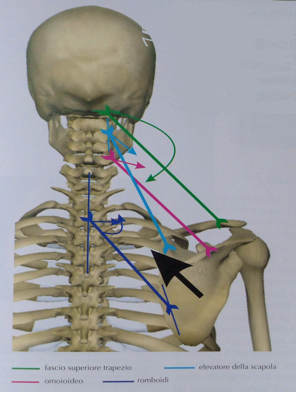

- DEVIAZIONI SUL PIANO FRONTALE E ROTAZIONI

In presenza invece di un dislocamento laterale della mandibola in chiusura, si ha uno stato di sofferenza a carico dei muscoli coinvolti con il dislocamento stesso (per esempio il temporale posteriore, il pterigoideo esterno omolaterali e temporale anteriore, pterigoideo interno controlaterali. )

Le ripercussioni sulla muscolatura del collo possono interesserare:

- il trapezio superiore omolaterale e sternocleidomastoideo controlaterale, così che la testa subirà una flessione dal lato della deviazione avvicinandosi alla spalla, che risulterà più alta della controlaterale.

- L’elevatore della scapola e gli scaleni omolaterali determinano la convessità vertebrale omolaterali da C1 a C7 e ruotano i corpi vertebrali omolateralmente. In queste condizioni la colonna vertebrale risulterà deviata sul tratto cervicale e inevitabilmente si formeranno altre curve compensatorie a livello toracico e lombare. Il coinvolgimento del rachide provocherà per via riflessa altri squilibri muscolari come per il gran dorsale.

moncone della spalla. Nel loro insieme questi muscoli hanno una risultante complessiva che determina l’elevazione in adduzione della scapola e l’elevazione della clavicola. Se interessato anche l’omoioideo, l’osso ioide sarà deviato lateralmente.

Frecce blu: risultante complessiva dell’azione degli elevatori del moncone della spalla e dei fasci superiori del gran dorsale.

Frecce rosa: azione dei fasci costo omerali del gran dorsale.

Frecce verdi: azione dei fasci inferiori del gran dorsale.

Frecce azzurre: azione dei fasci medi del trapezio e romboidi.

Frecce gialle: azione del dentato anteriore.